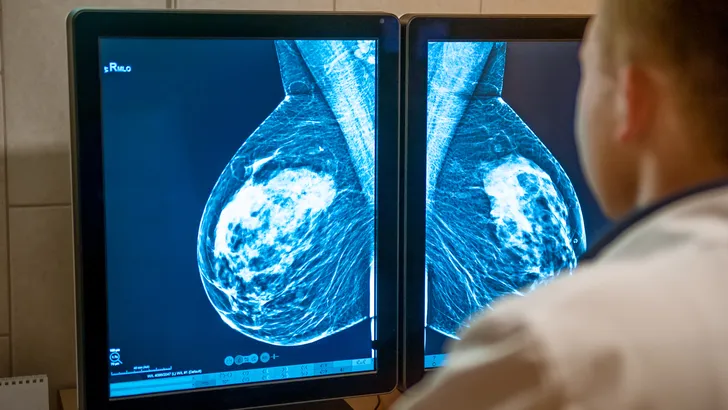

Stel je voor, een type borstkanker dat ongevoelig is voor de meest gebruikelijke hormoontherapieën. Dat is triple-negatieve borstkanker. Omdat de opties beperkt zijn, staat deze variant bekend als extra agressief en lastig te behandelen. Maar er gloort hoop aan de horizon.

Na intensief onderzoek, gepubliceerd in het prestigieuze tijdschrift NPJ Breast Cancer, hebben wetenschappers een specifiek eiwit ontmaskerd als de grote boosdoener: het ID4-eiwit.

Je kunt dit eiwit zien als de brandstof voor de tumor. Hoe meer ID4, hoe sneller de tumor groeit, zich verspreidt en zich verzet tegen behandelingen. Het logische idee van de onderzoekers: wat gebeurt er als we de brandstoftoevoer stoppen?